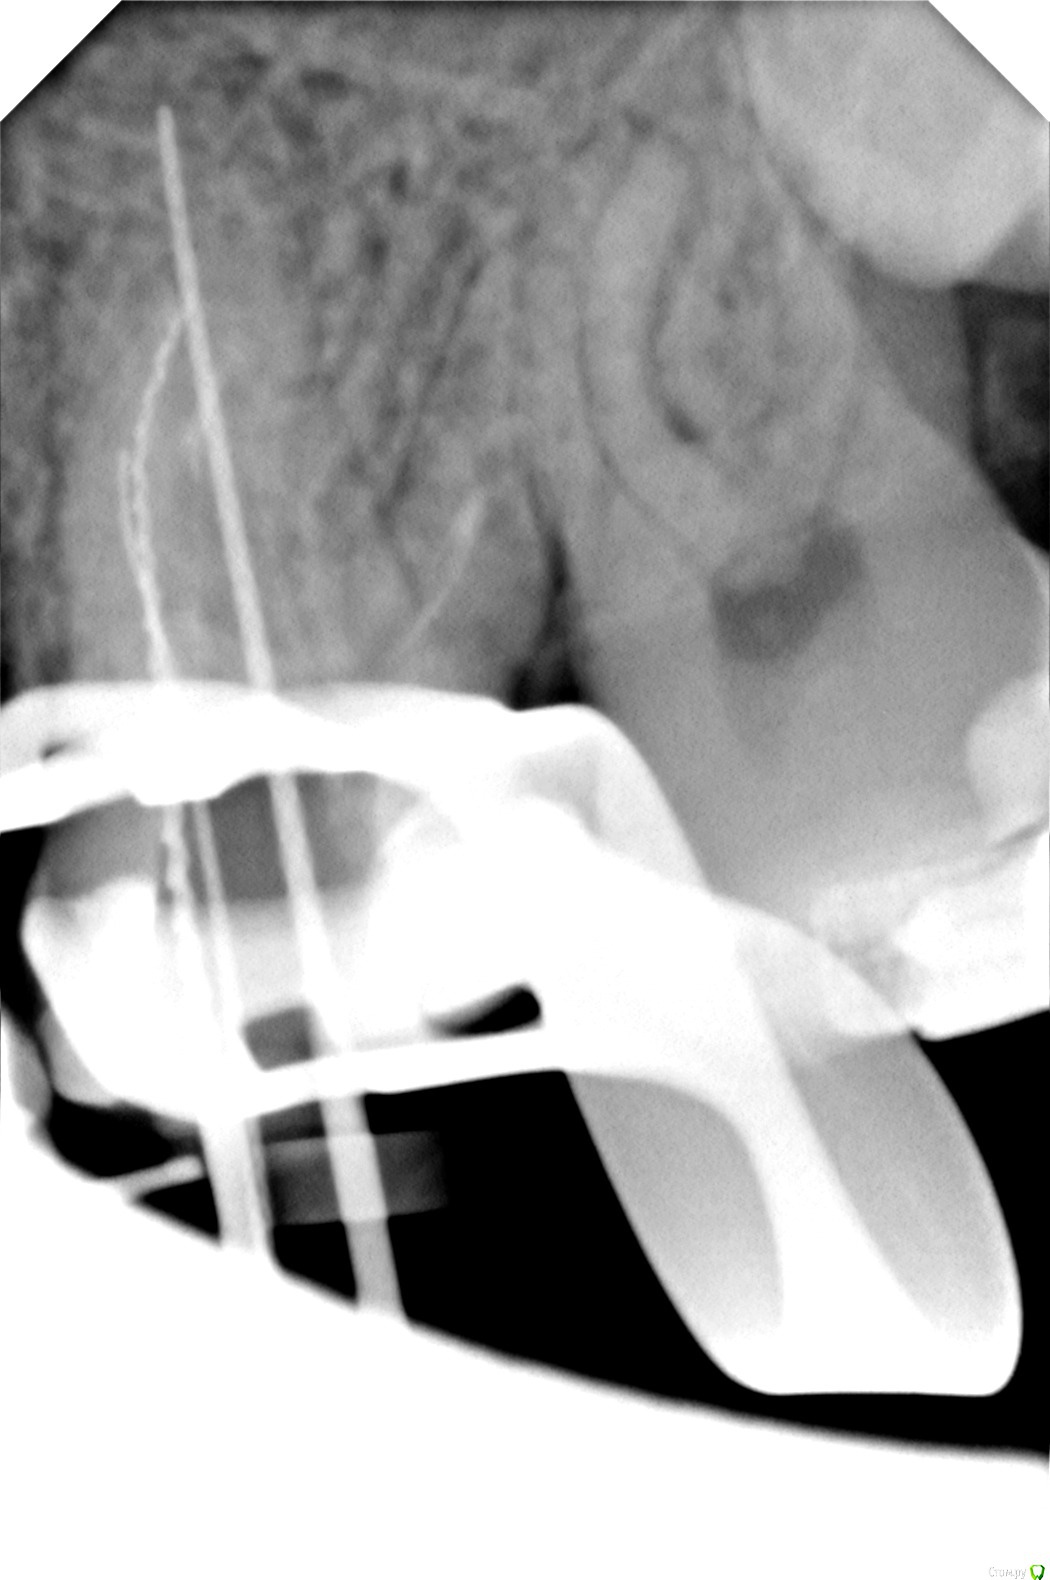

Axel_R Опубликовано 6 сентября, 2018 Автор Поделиться Опубликовано 6 сентября, 2018 Вот снимки на сегодня, зуб 26. Что скажете? Настаивать на высверливании старого материала из каналов или можно его спокойно оставить без негативных последствий? На зубе потом будет коронка. 1 1 Ссылка на комментарий

Axel_R Опубликовано 12 сентября, 2018 Автор Поделиться Опубликовано 12 сентября, 2018 Апдейт: Прошли 3 канала из 4, включая широкий небный. В оставшемся тонком канале говорят старый материал очень плотный и не поддается. На КТ и на снимках воспаления в районе верхушек тонких накалов не наблюдают и в других местах его тоже не видят. Форсировать не хотят, опасаются таки сделать перфорацию в тонком изогнутом канале. Поэтому доктор принял решение его оставить как есть и пломбировать пройденные. Ну Ок, им виднее. Но дело в том что зуб все еще болит когда кусаю что-то твердое! И никто не может назвать причину боли. Всегда думал сначала определяют в чем причина и устраняют эту причину, а уже потом пломбируют (ну как с кариесом). Я конечно мало в этом понимаю, но мне кажется если сейчас «замуровать» все вместе с источником боли, то ведь потом до этого источника уже будет не добраться (если он внутри канала или корня). А вдруг болеть будет еще неограниченно долго? Ведь не для этого я это лечение начинал…Я понимаю, что на повторное эндо нет гарантии и согласился с этим в документе, но как-то боязно... Вопрос: Правильное ли это решение? Соглашаться ли мне на пломбировку всех каналов когда зуб все еще болит? Ну или не соглашаться на завершение повторного эндо пока не устранят когда кусаю твердое? Какие будет мнения?Сама по себе пломбировка может устранить боль? Пока хожу с временной пломбой.На фото зуб в конце лечения с инструментами. Ссылка на комментарий